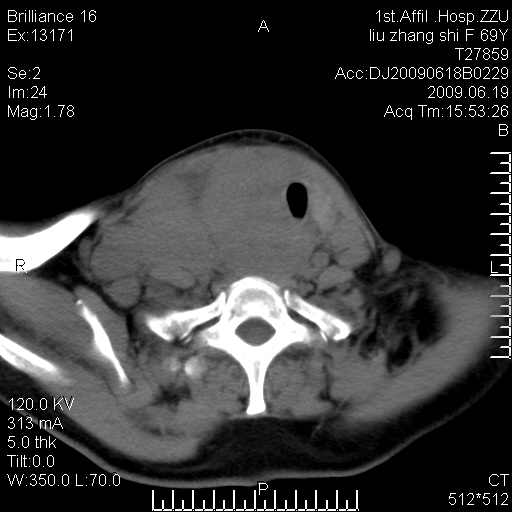

标题: CT26782:女,69岁,颈部占位,3天后公布病理结果。

【病理证实系列】女,69岁,颈部占位,有病理结果,3天后公布。(由于病例时间较久,临床资料不全,请网友见谅)本系列将有几百种常见、少见及罕见病例,均经病理证实。病例资料来自郑州大学第一附属医院。与网友共享,本人有空就发。

甲状腺癌并颈部淋巴结转移。感谢楼主的良苦用心,谢谢。

甲状腺癌并颈部淋巴结转移。

需与鼻咽癌鉴别!

支持甲状腺癌广泛侵及周围结构并颈部淋巴结转移。

鉴别:淋巴瘤、恶性神经源性病变、恶性纤维组织细胞瘤。

病理结果:颈部非霍奇金淋巴瘤。

右侧甲状腺确实有问题